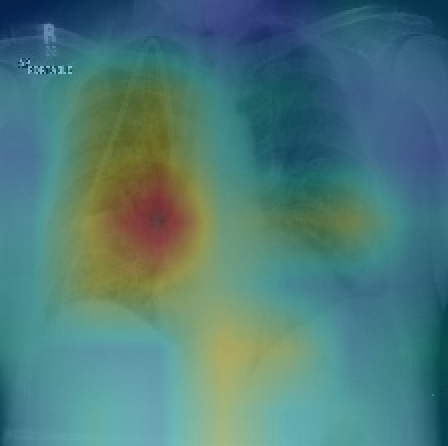

与此同时,为了解网络预测准确程度,网络还使用类激活映射(CAM)生成热图,以便可视化图像中与疾病最相关的区域[14]。为了生成CAM,将图像送到完全训练的网络中,并提取出最后一层卷积层输出的特征图。假设是第k个特征映射,并且令是第k次特征映射导致疾病c在最终分类层中的权重。模型通过使用相关权重对特征映射进行加权求和得到一个最明显的特征热图,用于将图像分类为疾病c。虽然模型网络最终能得到病理的热图,热值较高的区域即为可能发生疾病的区域,但并没有给出切割区域的准确结果,无法与原始切割效果做对比评判性能。

基于该模型的思想,单独的DenseNet网络能够得到较好的分类效果,并可以通过CAM技术画出网络学习到的热图来对病理区域进行分析。利用与DenseNet具有相似性质不仅模型深,同时复杂度也较低的ResNet网络也会得到类似的结果,其相关模型介绍见下一节。